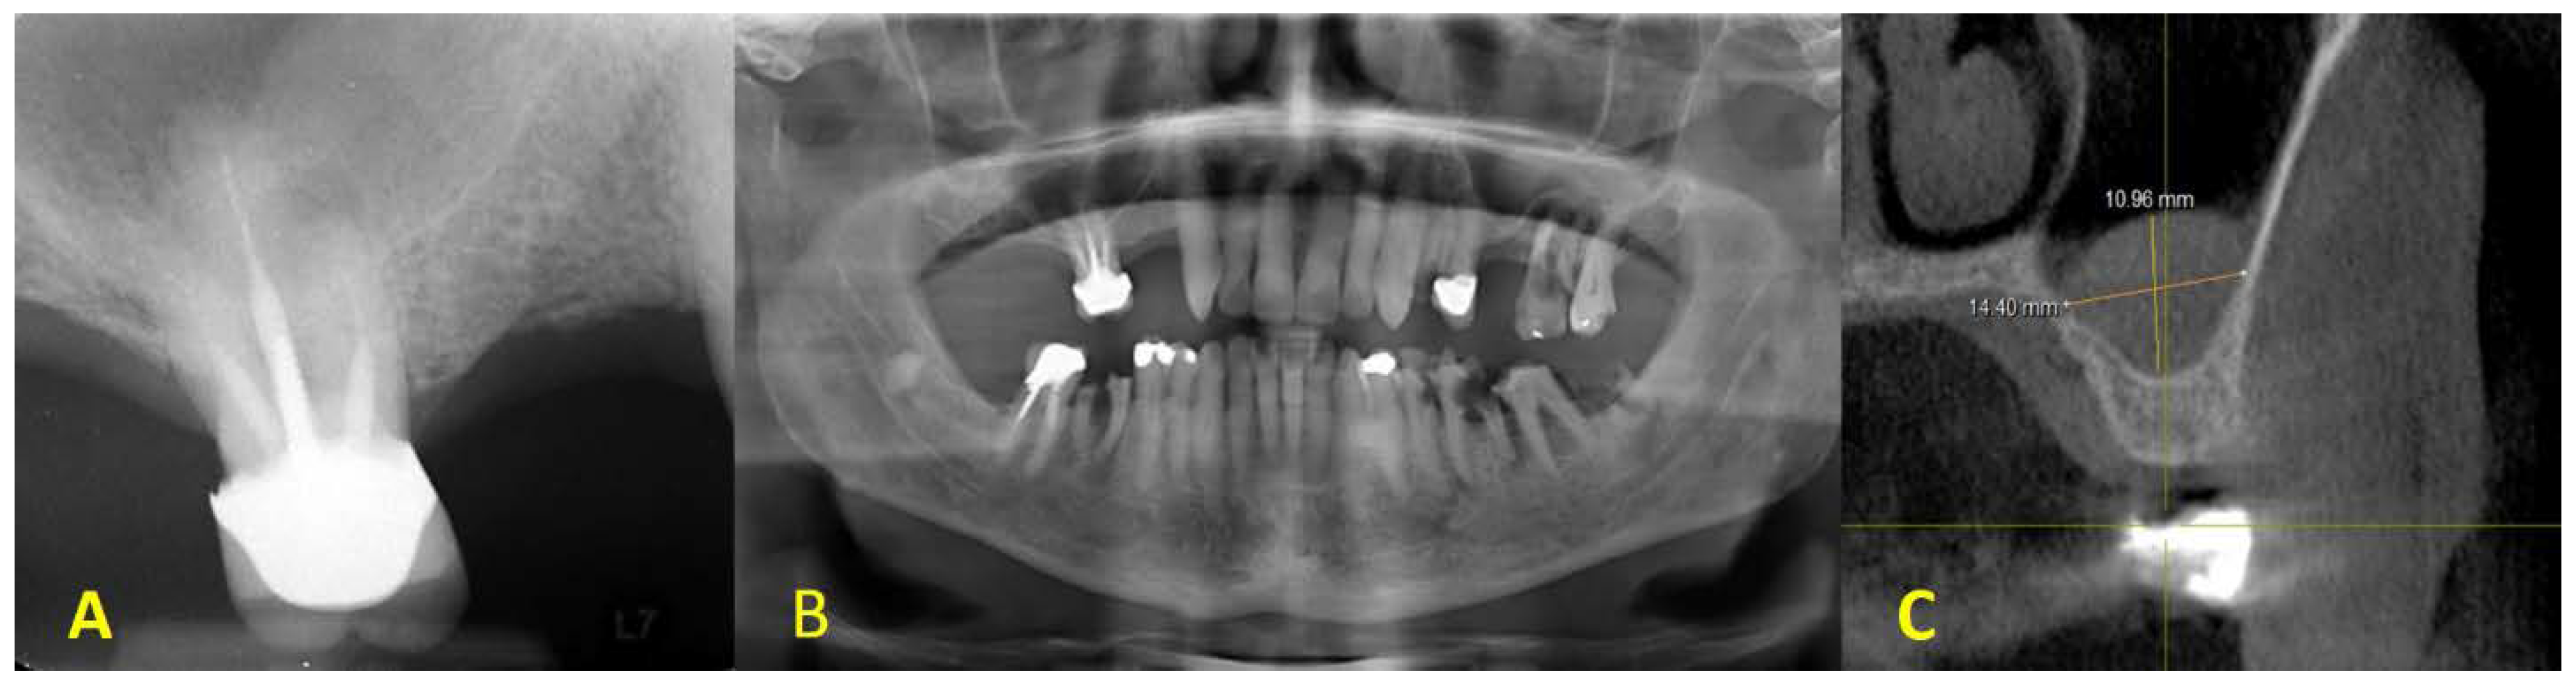

2. Clinical Presentation

3. Surgical Procedures